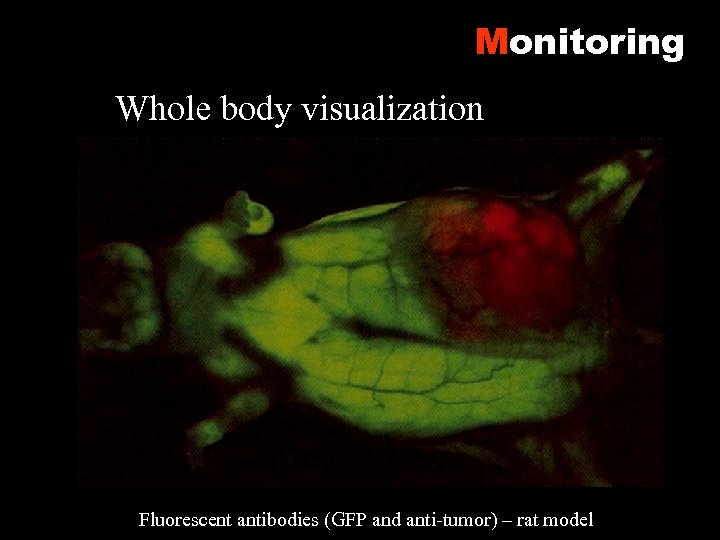

Monitoring Whole body visualization Fluorescent antibodies (GFP and anti-tumor) – rat model

Monitoring Whole body visualization Fluorescent antibodies (GFP and anti-tumor) – rat model

Monitoring Whole body visualization Fluorescent antibodies (GFP and anti-tumor) – rat model

Monitoring Whole body visualization Fluorescent antibodies (GFP and anti-tumor) – rat model